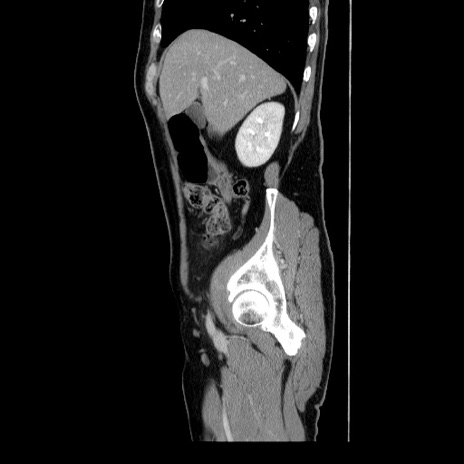

症例34(矢状断像)

【症例】60歳代 男性

【主訴】右鼠径部膨隆

【現病歴】1年程前より右鼠径部膨隆あり。自己にて還納可能だったため放置していた。3時間前より右鼠径部の脱出を認め、還納困難となり受診。

【身体所見】右鼠径部に小児頭大の膨隆あり。弾性硬であり、用手還納は困難。左鼠径部にも膨隆を認める。脱出はなし。